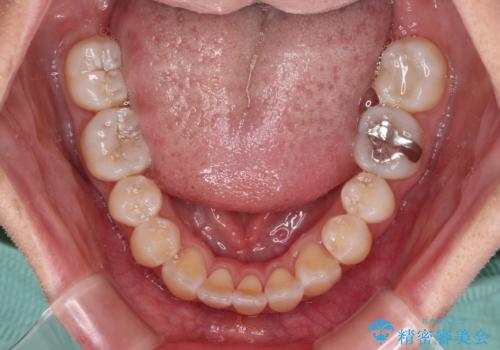

外に飛び出して磨きにくい奥歯と上下前歯の隙間 インビザラインによる矯正治療

- 上下前歯の隙間と、外側を向いていて歯磨きのしにくい奥歯を気にして来院された患者様です。

下顎前歯が1本欠損しており、上下アーチはアンバランスとなりますが、インビザラインを用いて上下の隙間を改善しながら歯列を整えることとしました。

外側を向いている奥歯は、内側にアンカースクリューを埋入して牽引の固定ゲント氏、部分的にワイヤー装置を用いることで歯列に納めることとしました。

下顎前歯の1本欠損により左右の咬合が不安定となり、治療経過で噛みにくい状態が続きましたが、最終的には違和感なく噛めるようになりました。